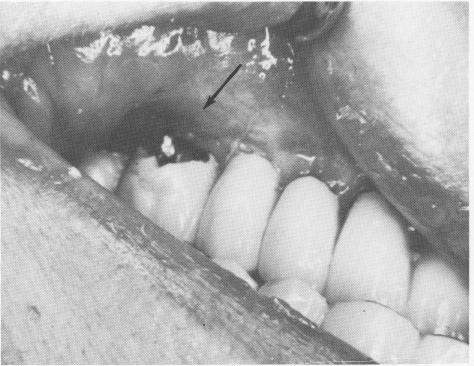

Fig. 7-93. To maintain the benefits of a full arch splint he right central incisor pontic was prepared for a ful :rown restoration without severing it from its mesial solder joint.